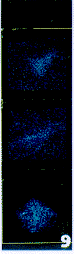

图9 5周模型组大鼠血清培养HSC TGF-β1的表达。

Fig.9 TGF-β1 expression in HSC culured by model sera for 5 weeks.

3. 在激光扫描共聚焦显微镜下,3周造模血清组培养的HSC呈很强的TGF-β1荧光,正常鼠血清组和5周造模血清组培养的TGF-β1荧光较弱(图6~9),7周造模血清组和添加药物鼠血清组的TGF-β1荧光极弱,在荧光激发下瞬间淬灭。

正常大鼠血清可使HSC表达低水平的TGF-β1。在造模3周时血清可强烈刺激HSC高水平表达TGF-β1。在形成肝纤维化时期血清即5周造模血清培养的HSC表达TGF-β1的能力迅速降低。随着纤维化的程度加重,假小叶的出现,第7周造模大鼠血清培养的HSC表达TGF-β1趋近于零。药物血清添加组HSC不表达TGF-β1。荧光强度显著性检验表明:造模3周血清组与正常和5周血清组比较,加药物3周血清组与未加药物3周血清组比较P值均小于0.01,有显著性差异。